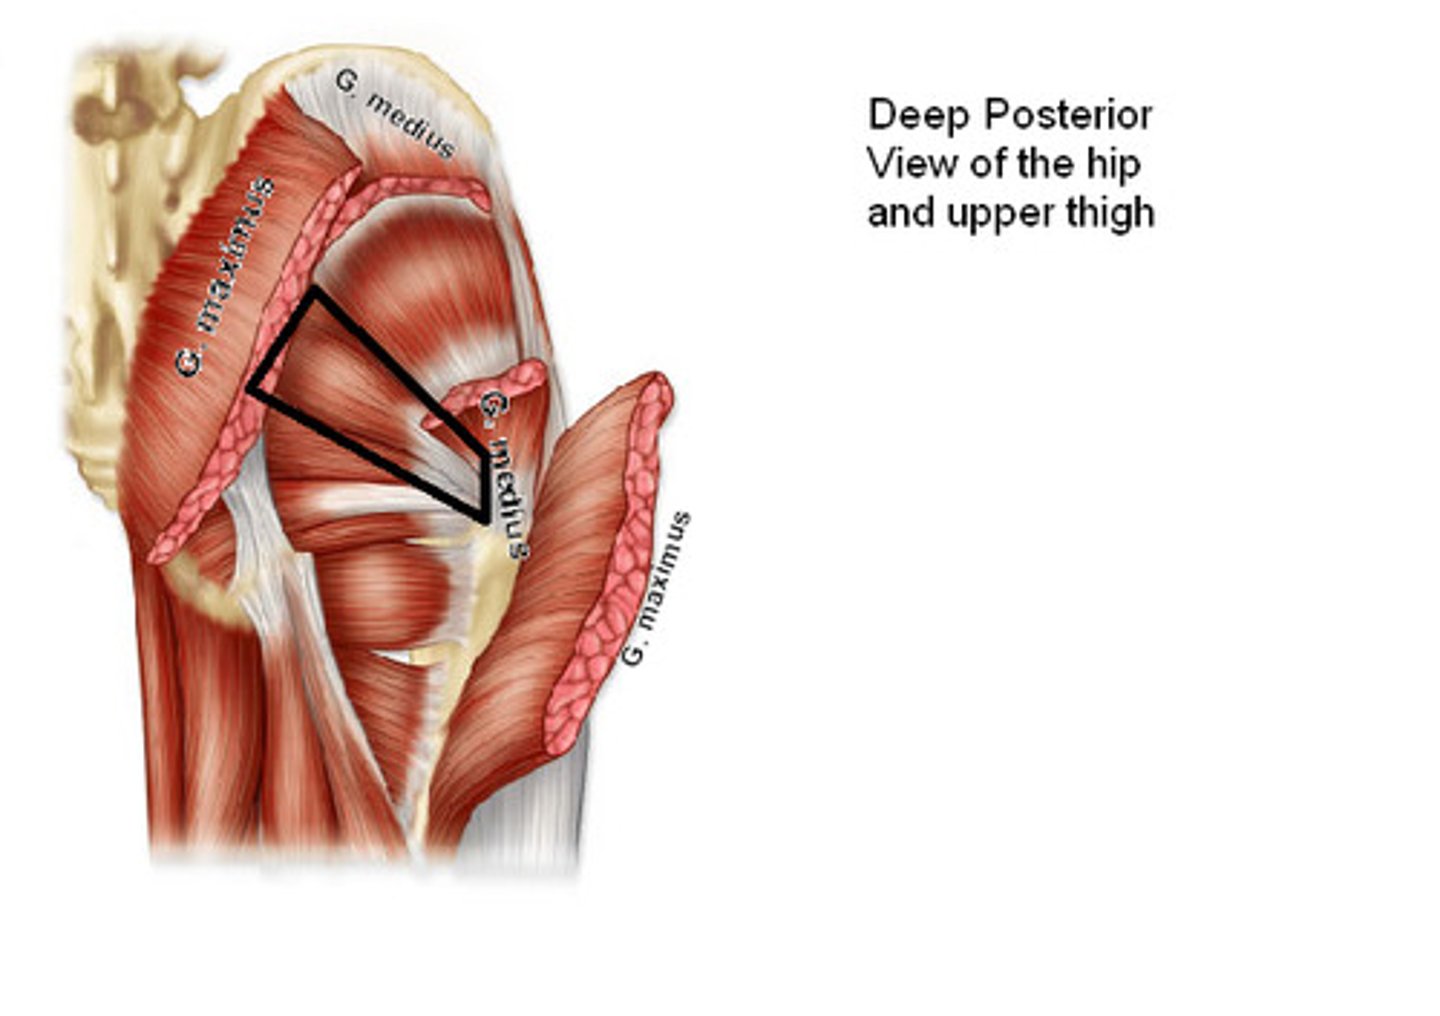

Gluteus maximus m.

Origin: illium/sacrum

Insertion: femur proximal end

Action: extend, rotate

Gluteus medius/minimus m.

Origin: ilium

Insertion: femur proximal end

Action: abduct, rotate

Piriformis m.

Origin: sacrum

Insertion: femur proximal end

Action: abduct, rotate

Obturator internus m.

Origin: obturator foramen edge

Insertion: femur proximal end

Action: abduct, rotate

Sup./inf. gemellus m.

Origin: ischium

Insertion: femur proximal end

Action: abduct, rotate

Quadratus femoris m.

Origin: ischium

Insertion: femur proximal end

Action: abduct, rotate